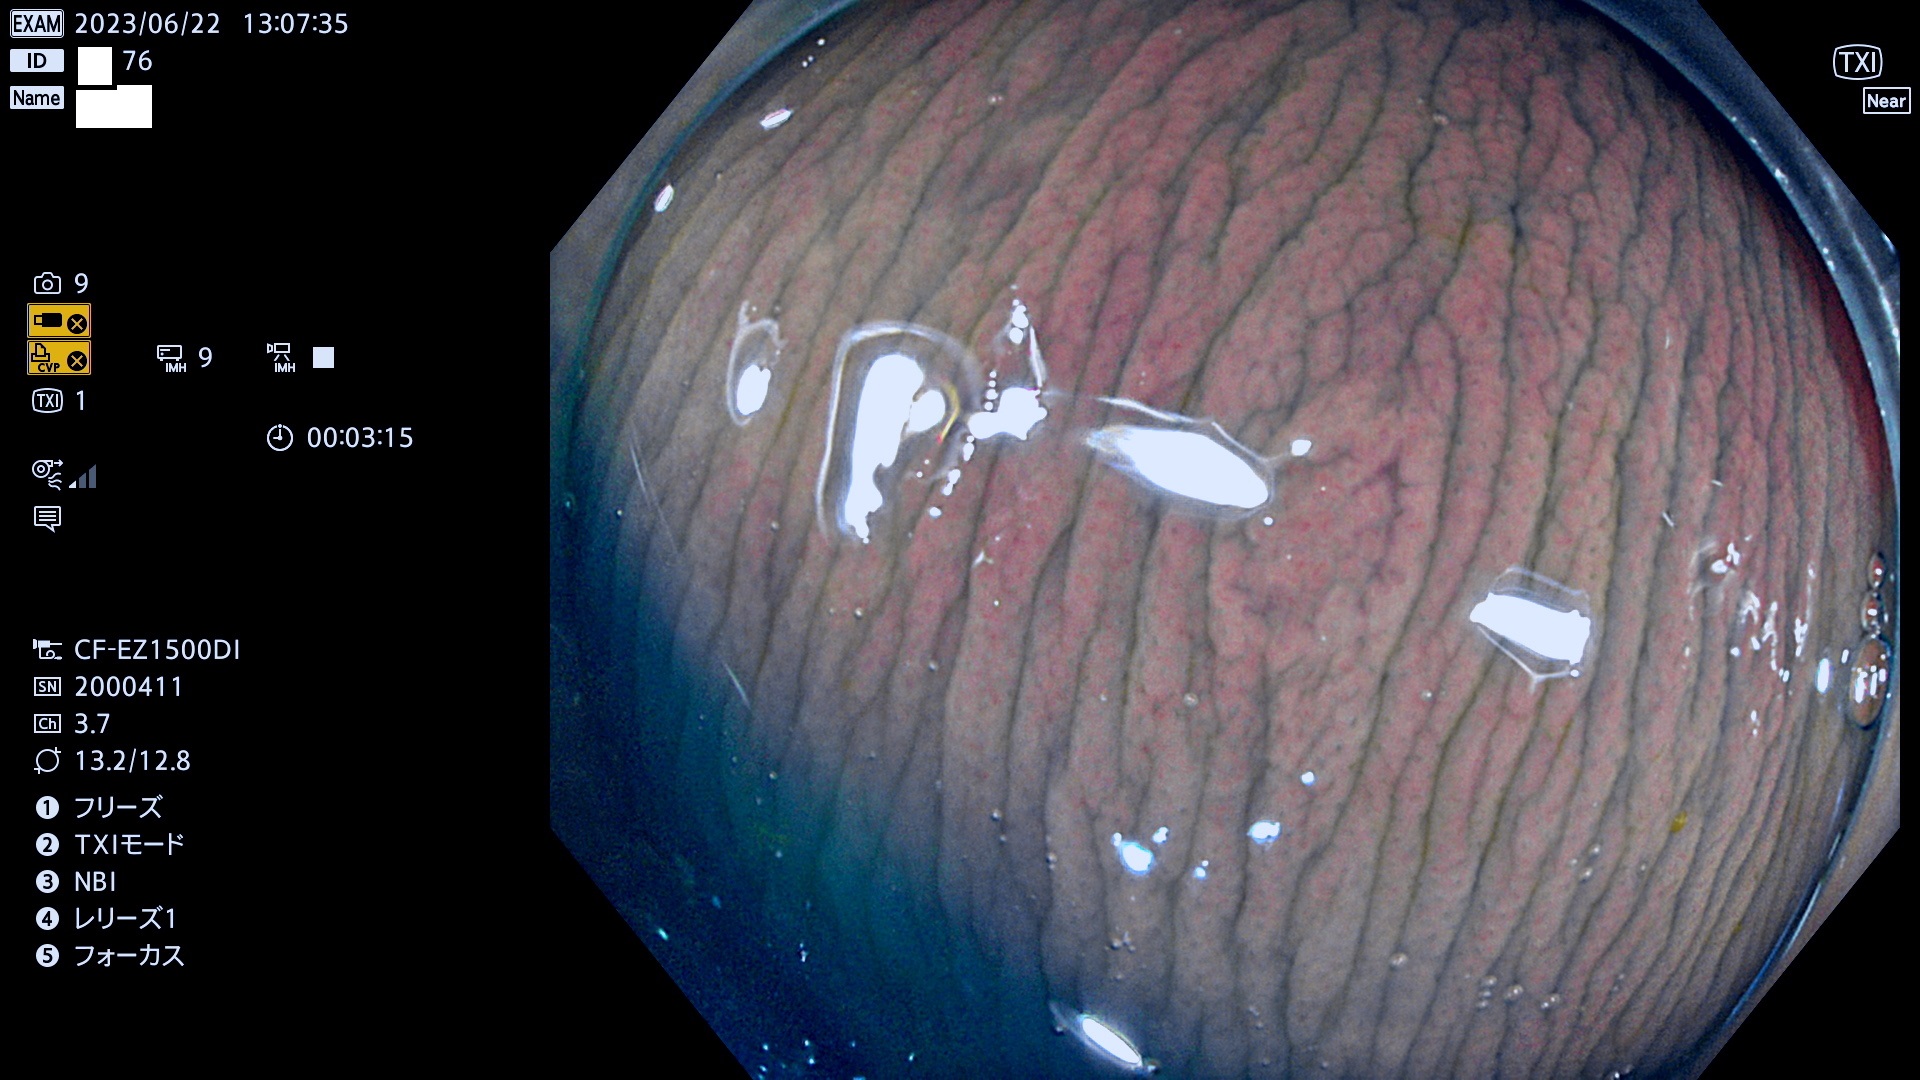

「表面型腫瘍」の中で、完全に平坦な物をUb、陥凹している物をUcと呼びます。平坦隆起型(Ua)よりも、発見が難しく危険な病変です。このタイプの発見率は「腺腫発見率」よりも、遥かに重要な意義があります。

抽出の対象期間 2023年6月22日(木)〜25(日)の4日間(48件の検査)5件

当サイトは以前は「腺腫発見率」を定期公開していました。「Ub,Uc発見率」は検査の品質指標として、遥かに重要であり、医師にとっても非常にシビアです。定期公開の目的は、検査精度の維持です。これにより医師は常に、「Ub,Ucを見つける!」という緊張感・動機をもって、検査に望む訳です(Ub,Ucを探せば、他の形態の病変は容易に見つかります。このような趣旨なので形態診断学的には厳密ではありません)。